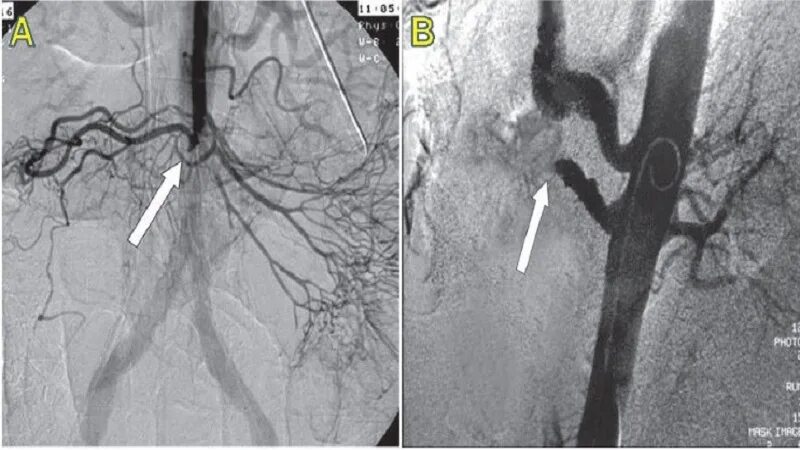

Тромбоз брыжеечной артерии